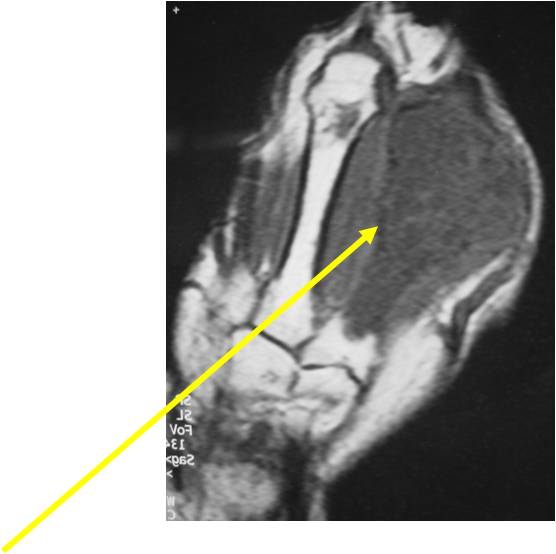

- T2 Weighted Images: High Signal Intensity

- High water content shows as high signal on T2 weighted images

- Calcifications will be low signal

- There should never be any cortical destruction nor a soft tissue component. If this exists then the tumor must be a chondrosarcoma.

- Endosteal scalloping and cortical expansion is acceptable for phalangeal tumors. In most benign long bone cartilage tumors there is minimal endosteal scalloping but there should be no cortical expansion nor thickening. There should be no cortical destruction and no soft tissue component associated with an enchondroma. Cortical destruction, periosteal thickening, cortical expansion and a soft tissue component indicates a chondrosarcoma of the long bone.

T2: High Signal No Soft Tissue Component